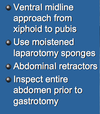

Surgical Technique for Gastric Dilatation Volvulus Described Below:

Incision through Right Abdominal Wall Caudal to Last Rib

Purse String Suture in Stomach

Place Foley or Mushroom Tip Catheter

Suture Stomach to Abdominal Wall

The Tube is Clamped and Bandaged

Tube Prevents Recurrent Dilatation

Tube Gastropexy